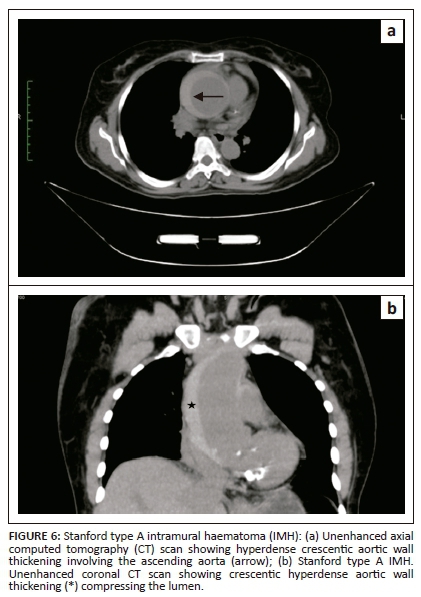

Crescentic aortic wall thickening of increased attenuation is the most vital finding on unenhanced CT scan images (Figures 6 and 8a). The lesion will displace intimal calcifications internally, if present. On contrast-enhanced images, the aortic lumen appears narrow without enhancement of the lesion (Figures 7 and 8b). On contrast-enhanced CT, it is difficult to distinguish between a thrombosed false lumen of AD and IMH. Aortic dissection follows a spiral longitudinal course, whereas IMH has a constant circumferential relation to the aortic wall which may aid in differentiation.11